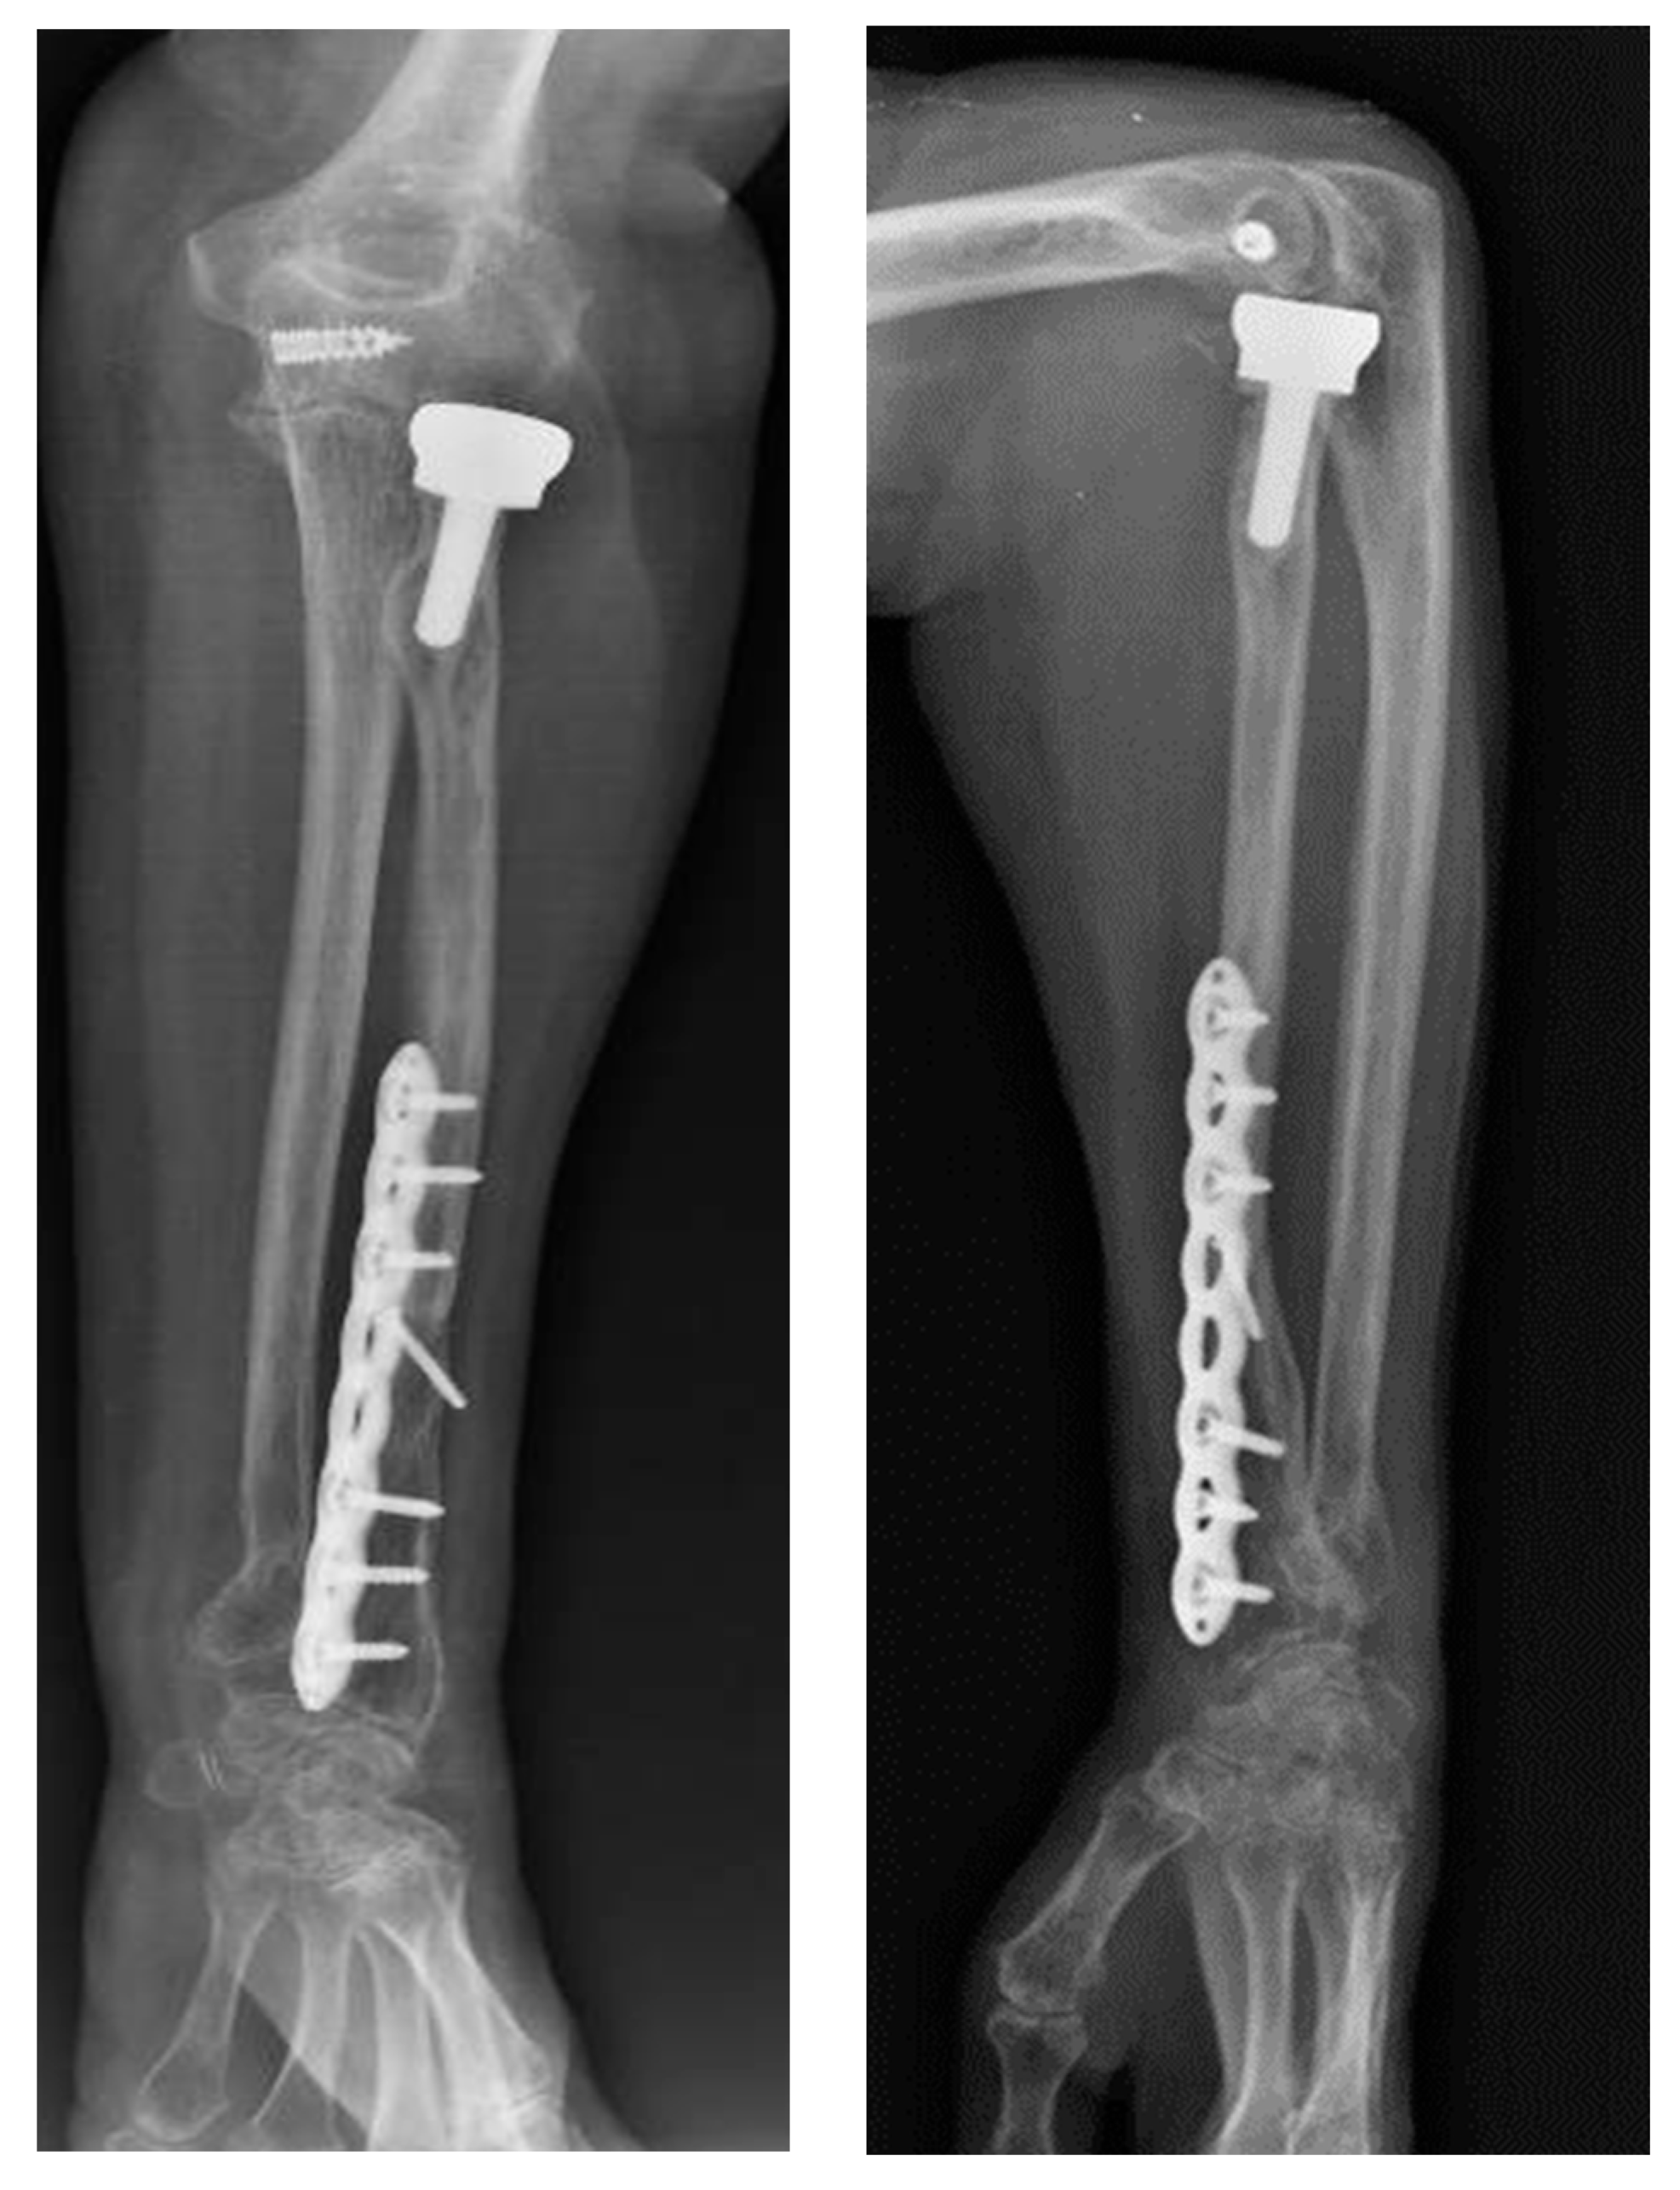

Upon physical examination, the patient exhibited a gross deformity of the left arm, with tenderness localized to the olecranon and wrist regions. The limb demonstrated complete functional impairment, with limited movement and significant swelling. Radiographic evaluation, including urgent X-rays, revealed a comminuted fracture of the distal third of the radius with dorsal displacement of the distal fragment and a comminuted fracture of the distal ulna metaphysis. Additionally, there was a multi-fragmentary radial head fracture, accompanied by partial detachment of the articular head, which raised concern for significant instability (Figure 1 and Figure 2). Based on these findings, a diagnosis of complex forearm fracture/dislocation with suspected longitudinal instability was made.

Figure 1. X-rays performed at the emergency room entrance.